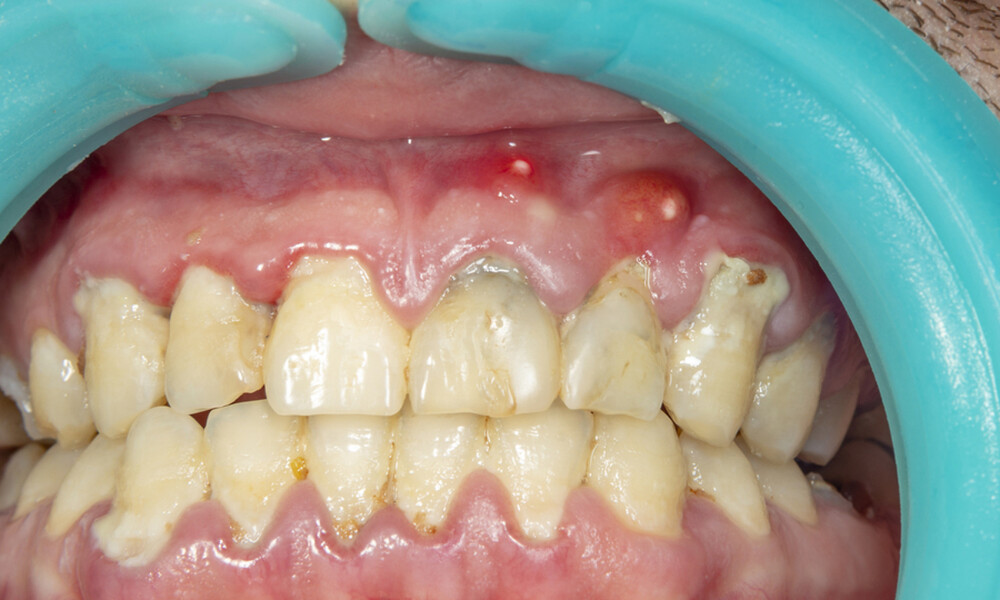

Η συγκέντρωση πύου στα ούλα ή στη ρίζα του δοντιού, που οφείλεται στην ύπαρξη φλεγμονής, ονομάζεται απόστημα.

Τα αποστήματα εμφανίζονται συνήθως μετά από οδοντιατρική χειρουργική επέμβαση, εξαιτίας λοίμωξης των ούλων, τραυματισμού ή φθοράς των δοντιών.